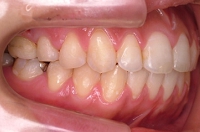

CASE3

前歯1本だけが出ています、矯正で治りますか?

(23歳/女性)↓

||||||||

概要・担当医コメント:

前歯の唇側傾斜/マルチブラケット装置/非抜歯

動的治療期間15ヶ月(15回)/費用概算:60万円.

歯列アーチの形態修正に必要なスペースを微量のエナメル質の研磨により創生し,当初の計画通りに歯を移動させました.